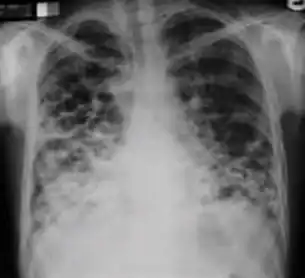

7. Other - Any other finding suggestive of active TB, such as miliary TB. Miliary findings are nodules of millet size (1 to 2 millimeters) distributed throughout the parenchyma.

In active pulmonary TB, infiltrates or consolidations and/or cavities are often seen in the upper lungs with or without mediastinal or hilar lymphadenopathy.[1] However, lesions may appear anywhere in the lungs. In HIV and other immunosuppressed persons, any abnormality may indicate TB or the chest X-ray may even appear entirely normal.[1]